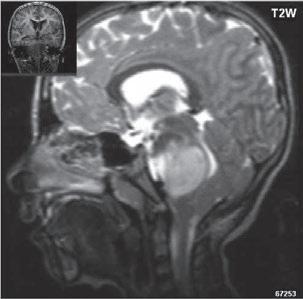

I.11 Patologické procesy selární oblasti . . . . 309

I 11 3 Makroadenom hypofýzy

Optochiasmaticko-hypothalamický gliom